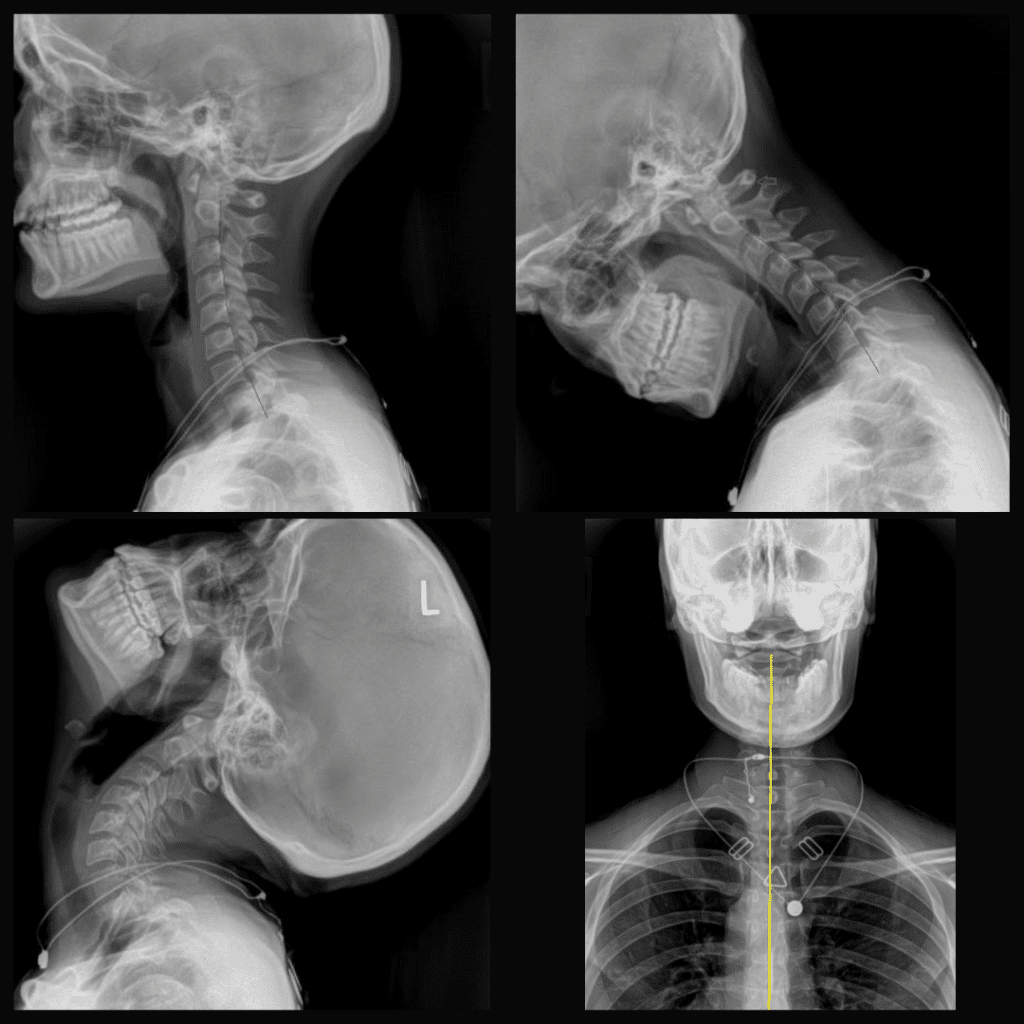

At a chiropractic symposium that she recently attended in New Jersey; she had an updated DDR motion x-ray study done to make sure that she puts her money where her mouth is. She talks every single day about having a strong and healthy nervous system and what that looks like, but what does hers look like? We wanted to show you her updated x-rays so that you are able to see that she doesn’t just preach it, but she lives it.

Dr. Marie was very fortunate to get under specific PRS care (the care that she provides in the office) throughout chiropractic school and has been under great care since. Her neck has a nice banana shaped curve in it and every bone in her neck moves extremely well… besides 1 bone. Which bone is that? Her atlas, C1 vertebrae. If you have been a patient in our office, you may have heard me talk about birth and how it can be very stressful on the infant, especially the upper neck of that infant. Well, sure enough, Dr. Marie was a c- section birth. When a C-section is performed, the OB is quite literally pulling an infant from their neck and twisting that infant’s neck to get them out. That pulling and twisting of the baby’s neck can put 60-90lbs of pressure on the neck, which can easily lead to a misalignment of that upper bone/s (C1 or C2) in the neck. This is most likely what happened with Dr. Marie’s atlas vertebrae. It was misaligned at birth and has likely been locked up since. Because it was locked up for approximately 20-25 years prior to her getting it addressed, it will most likely never move 100% properly again. However, to keep as much movement in it as we can right now to help prevent other issues from arising down the road. This is why she still gets checked and adjusted to keep her spine and nervous system functioning at its’ optimal potential.